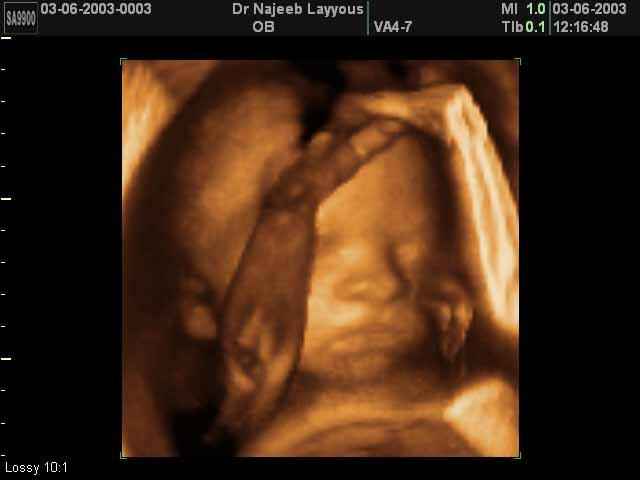

صور لوجه الجنين بجهاز الالتراساوند ثلاثي الأبعاد | الدكتور نجيب ليوس

صور لوجه الجنين بجهاز الموجات فوق صوتية ثلاثي الأبعاد